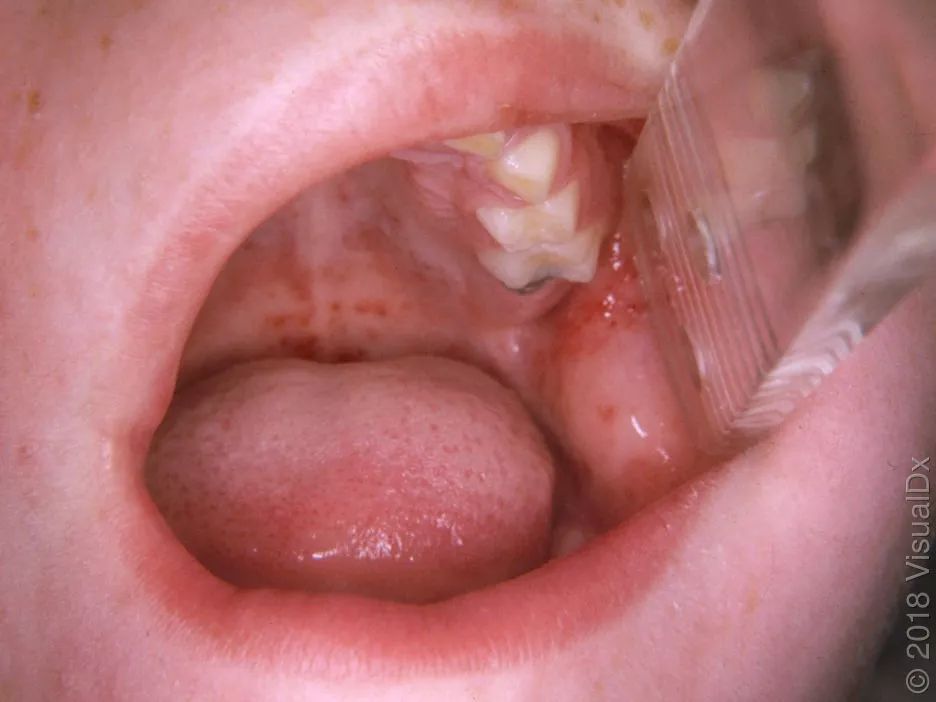

同一病人,颊黏膜koplik斑:第二臼齿对面的颊黏膜上蓝白色或紫色小点

图片来源见水印但是麻疹时更典型的是麻疹黏膜斑,表现是颊黏膜上,细盐